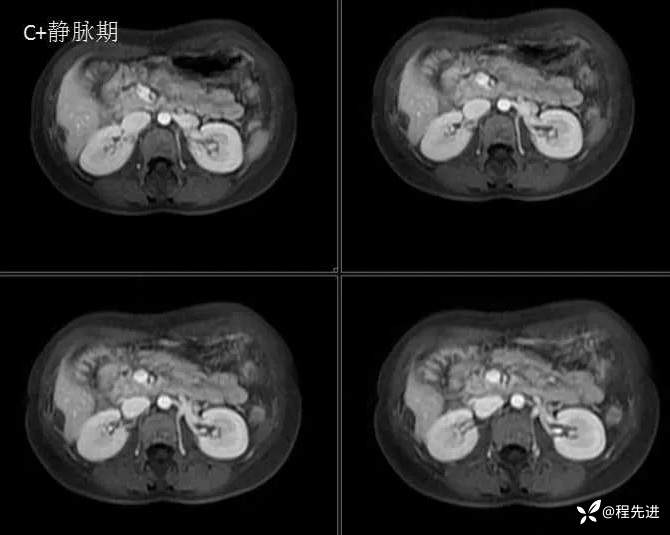

MRI检查: